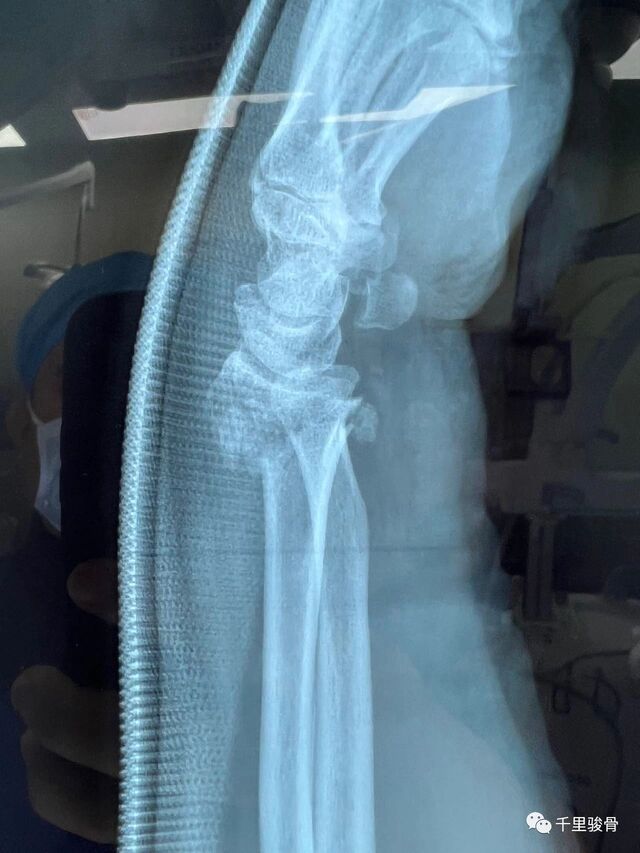

麻醉下透视复位

微信图片_20240102194812.jpg

微信图片_20240102194819.jpg